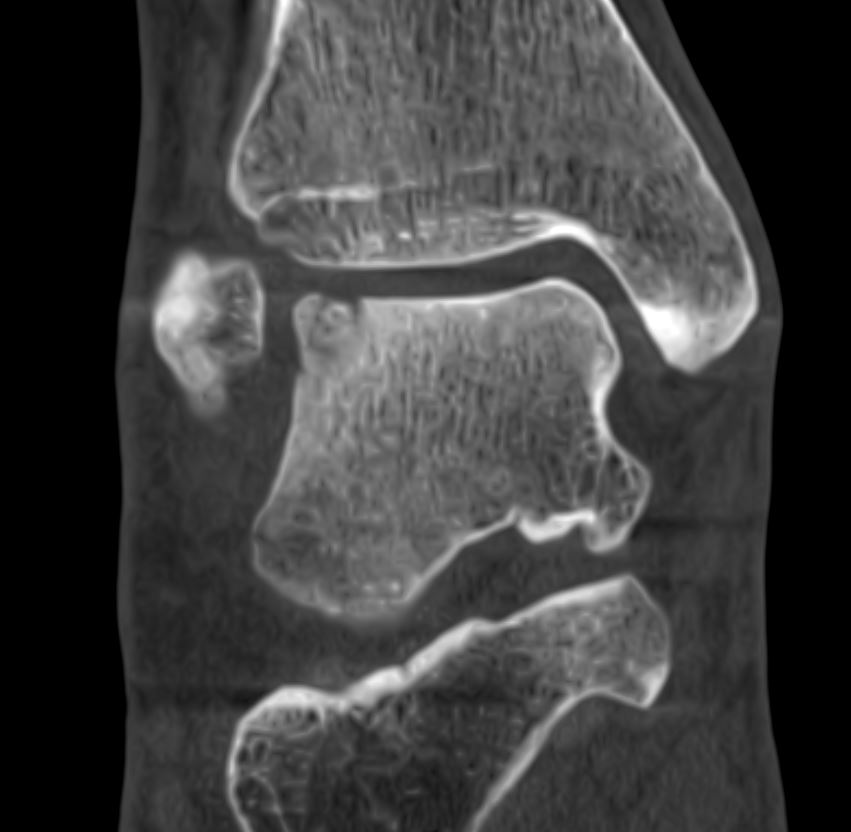

Home Schwerpunkte Krankheitsbilder Osteochondrale Läsion des Talus (OCL) – Ursachen, Symptome, MRT/DVT-Diagnostik & moderne Therapie posttraumatische OCL lateral

posttraumatische OCL lateral